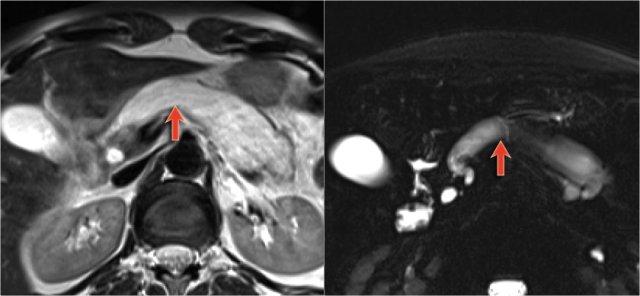

MRI better demonstrates the morphologic features of the lesion (fig).

On T2WI the lesion is multicystic.

Note the central low signal due to the central scar with calcifications.

Although some of the cysts are rather large, this is still a characteristic appearance of a serous cystic adenoma (macrocystic form).

Another example of a serous cystic neoplasm (Fig).

The contrast-enhanced image on the right shows a hypodense lesion with central calcification in the body of the pancreas and subtle enhancement of septations

Notice that on CT it is very difficult to appreciate the cystic nature of these lesions and you might think that you are dealing with a pancreatic adenocarcinoma.

MRI will easily demonstrate the cystic nature of these lesions (fig).

The T2WI with fatsat nicely demonstrates a lobulated hyperintense lesion with central scar, which is characteristic of a SCN.